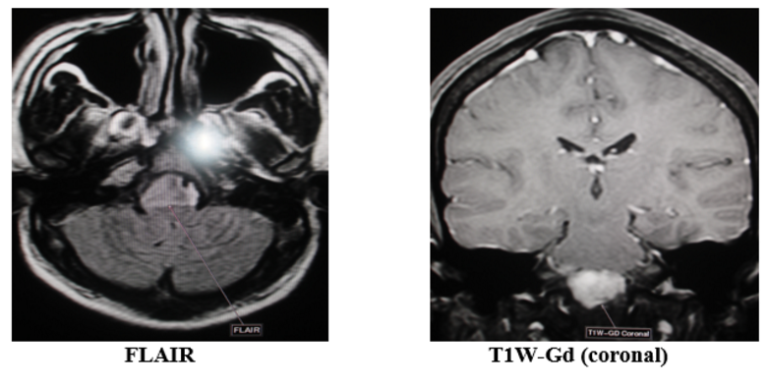

Nhân một trường hợp hẹp động mạch đốt sống Ngày 22/12/2016, Bệnh viện quân y 121 đã tiếp nhận bệnh nhân Đoàn Hữu N, sinh năm 1962, thường trú tại Ấp phước Hòa, xã Hòa Phú, huyện Long Hồ, tỉnh Vĩnh…